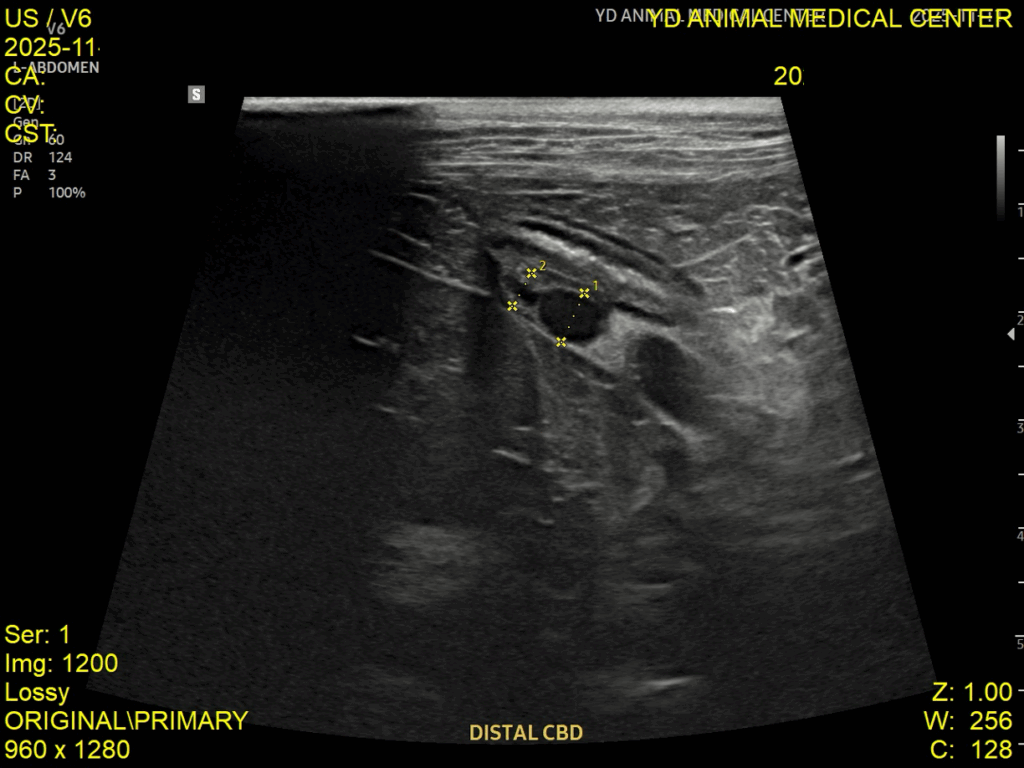

고양이 EHBO, 담낭 및 담도 내 슬러지 치료 케이스 – 강서구 동물병원

고양이가 갑자기 구토를 반복하거나 식욕이 떨어지는 모습을 보이면 단순 위장 문제로 생각하기 쉽습니다. 하지만 이러한 증상이 며칠 이상 이어지거나 반복된다면 단순 소화 문제를 넘어 담도계 질환이나 췌장 질환처럼 보다 정밀한 평가가 필요한 상황일 수 있습니다. 오늘은 담관 폐색(EHBO)과 담낭 슬러지가 함께 확인되었고, 치료 후 현재까지 안정적으로 관리되고 있는 고양이의 실제 케이스를 소개드리겠습니다. 실제 케이스: EHBO(담관 […]